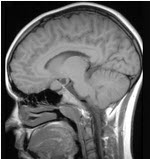

关于星形细胞瘤(如图所示)的描述错误的是()

A:肿瘤多呈浸润性生长

B:可分为纤维型、原浆型、肥胖细胞型

C:主要位于灰质内

D:实性者无明显边界

E:可不限于一个脑叶